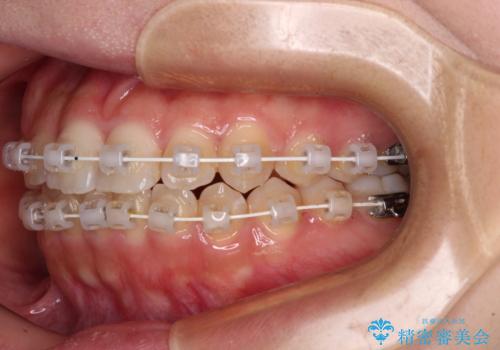

- 矯正装置

- 審美装置

- 1年1ヶ月

- 前歯のデコボコを気にして来院された患者様です。

マウスピース矯正のような自己管理の煩わしさがなく、早く治療を終えたいとのことで、ワイヤー装置による矯正治療を行うこととしました。

当初予定通り、1年で治療を終えることができました。

後戻り防止はマウスピースで行うため、急に自己管理が必要となるため、移動の最後をマウスピース矯正で行うことで、マウスピース非装着による後戻りリスクを回避する工夫をしています。